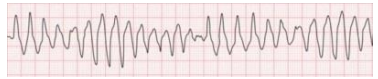

melhora da agitação, porém com alteração no traçado da

cardioscopia.

Após a troca da monitorização para o carro de emergência, é

impresso o ECG da imagem:

Eletrocardiograma contínuo de uma derivação, traçado sem onda

P visualizada, com QRS alargado e amplitudes progressivamente

variáveis, ora com aumento progressivo, ora com diminuição

progressiva.

melhora da agitação, porém com alteração no traçado da

cardioscopia.

Após a troca da monitorização para o carro de emergência, é

impresso o ECG da imagem:

Eletrocardiograma contínuo de uma derivação, traçado sem onda

P visualizada, com QRS alargado e amplitudes progressivamente

variáveis, ora com aumento progressivo, ora com diminuição

progressiva.